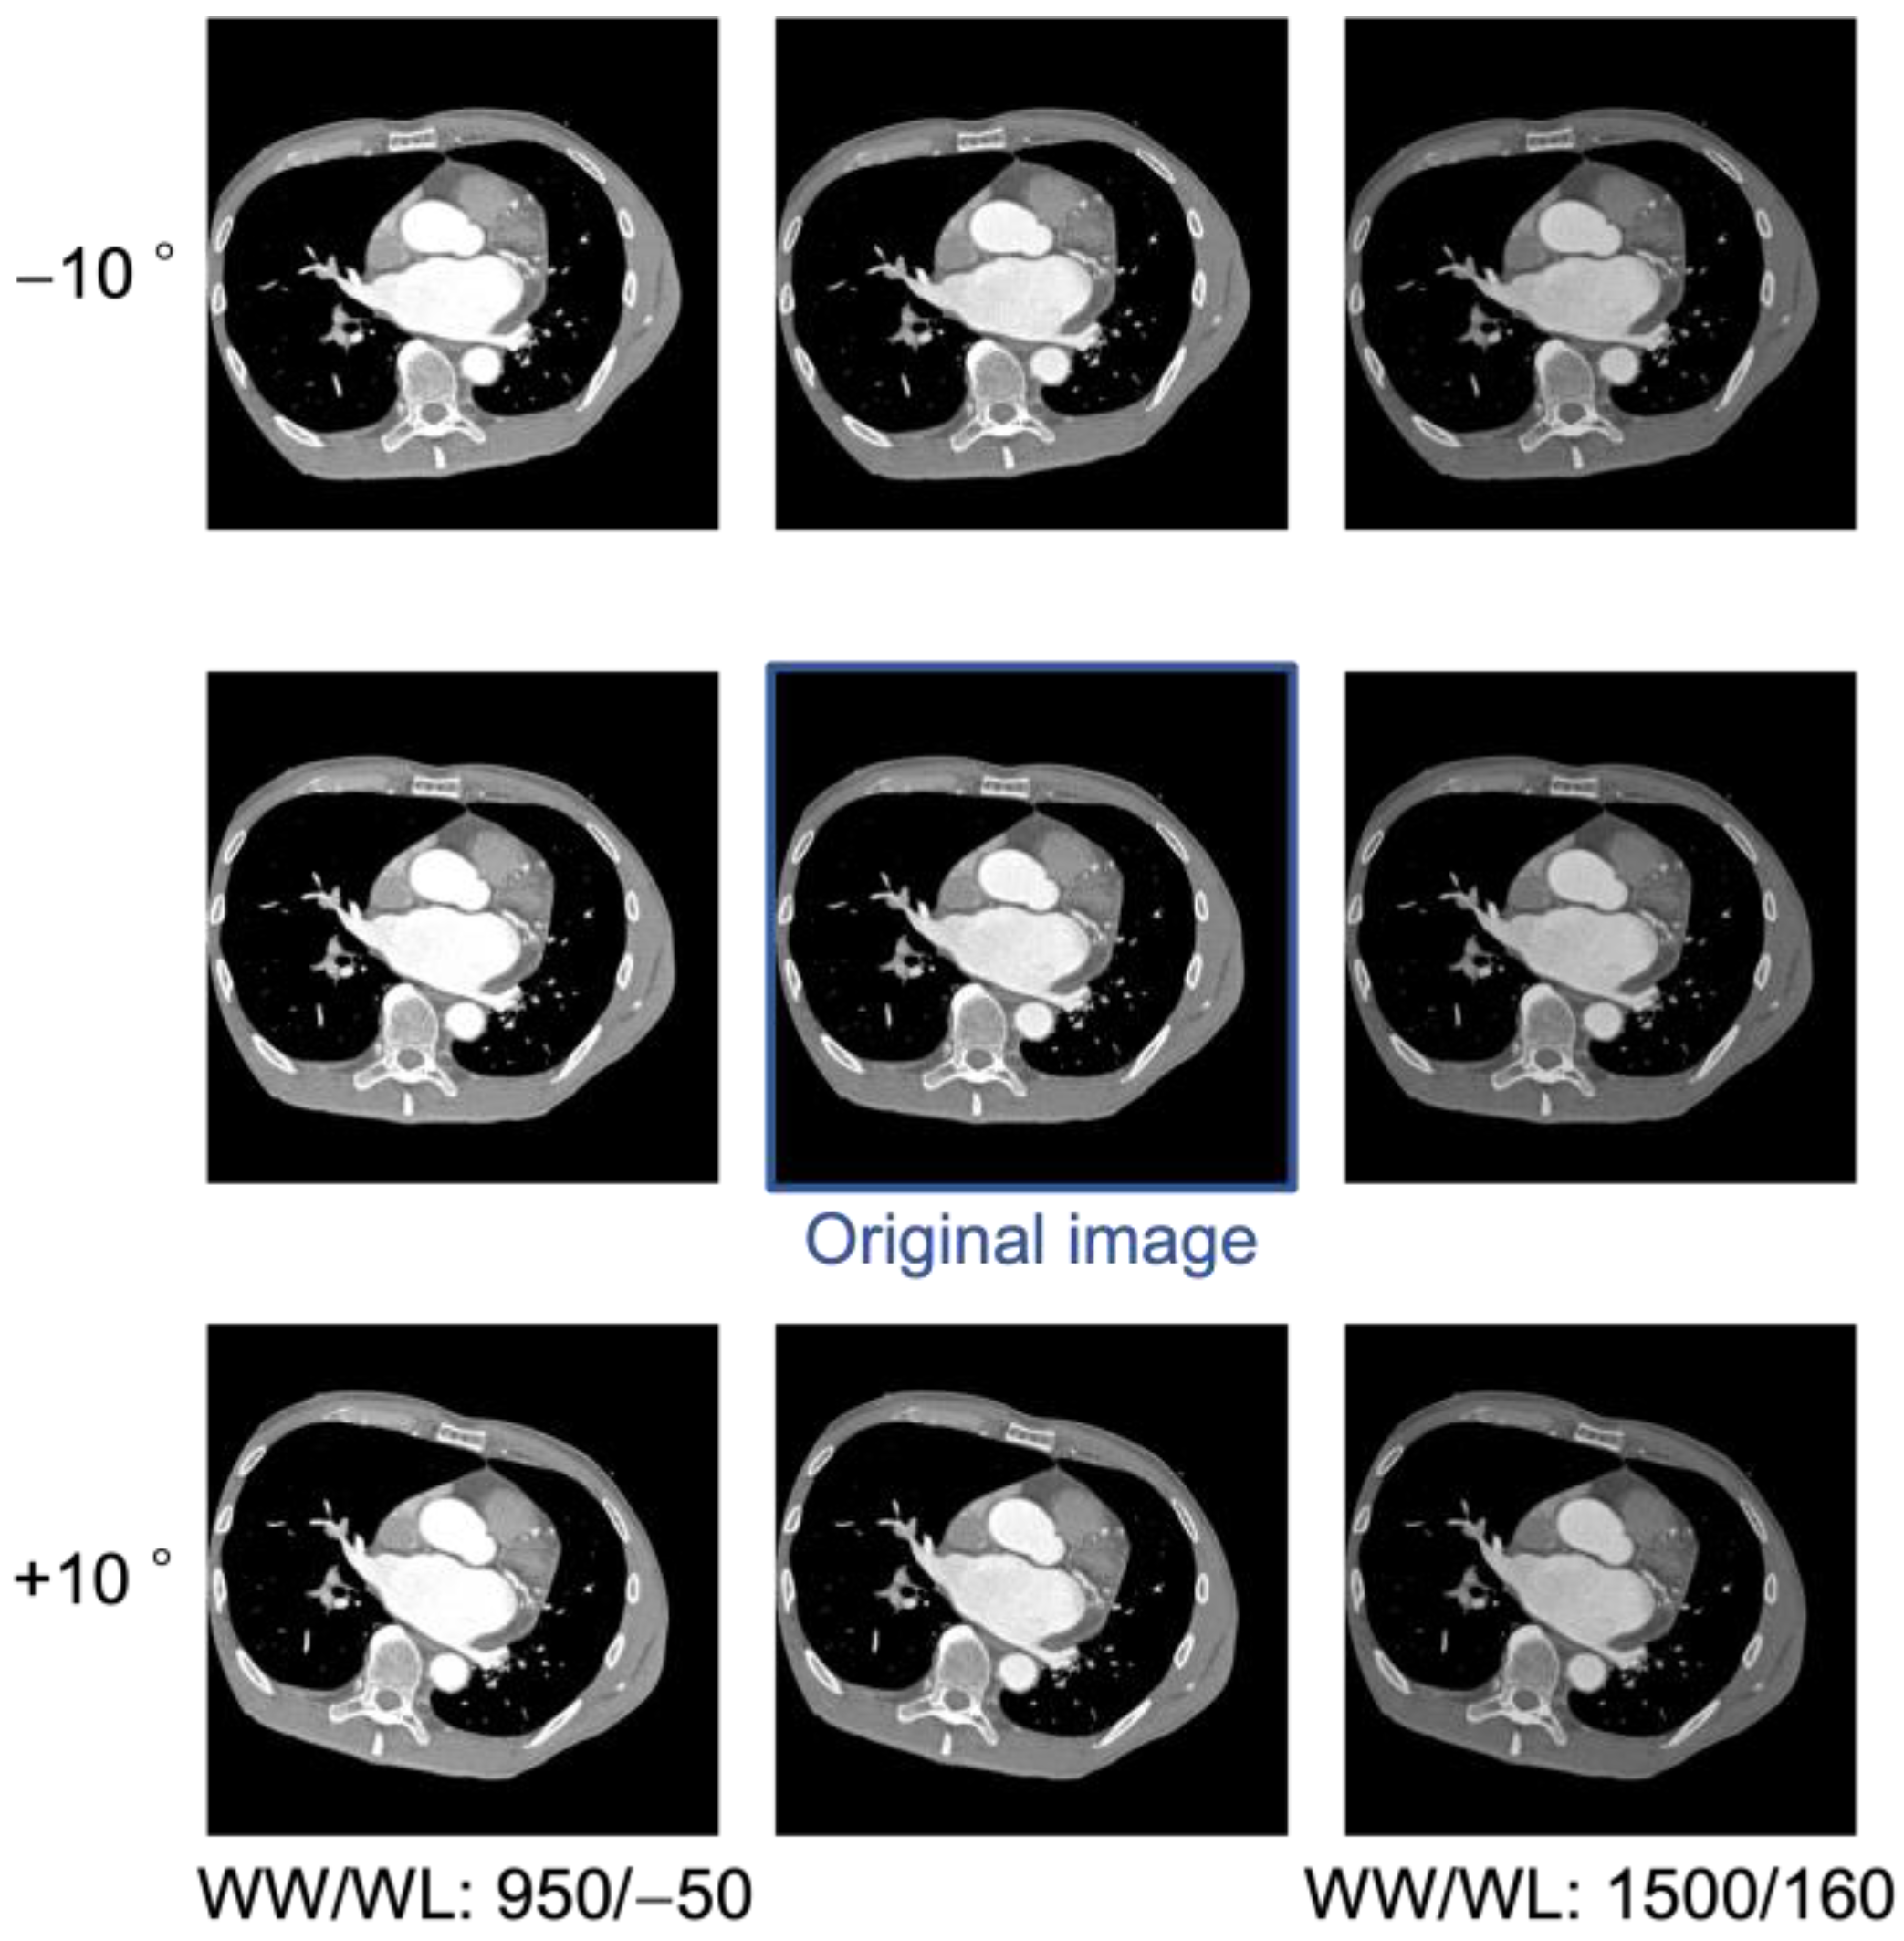

2.3.2. Data Augmentation

Data augmentation is a method of increasing data by “transforming” image data for training. For example, by rotating, flipping, shifting horizontally, scaling, distorting, adjusting brightness and contrast, and adding noise to an image, various variations can be created. In this study, the number of images increased nine times through data augmentation [19]. CT examinations are usually performed in the supine position; however, in some facilities, the patient is positioned so that the heart, which is located on the left side of the body, is centered in the FOV. In such cases, the curvature of the bed may cause the body to rotate about 10°. To simulate this, the heart was rotated by −10° and +10° for each image, aligning the heart’s tilt to match that observed in the actual CT image. In contrast-enhanced CT examinations, since the density of the contrast agent varies depending on the case, we augmented the pixel values to be robust to changes in pixel values. The CT values of the left atrium were observed across the entire dataset, and the window level (WL) and window width (WW) were adjusted so that the CT values after augmentation fell within the range of real CT images. As a result, in addition to the initial condition of WL = 30, WW = 1000, two variations, including WL = −50, WW = 950 and WL = 160, WW = 1500, were added to increase the number of images threefold. An example of the created image is shown in Figure 2.

Figure 2.

Examples of an original image and images created using data augmentation.